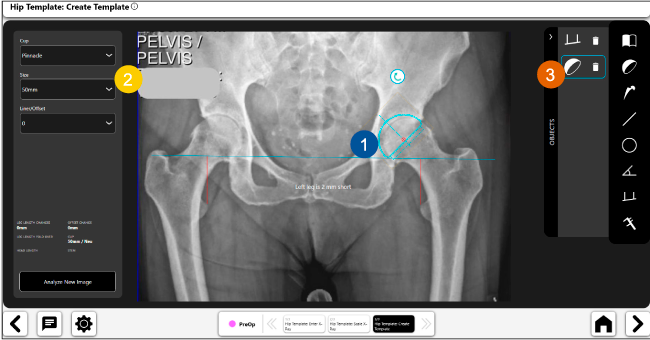

Disponibilidad de plantillas digitales de cadera.

Expediente histórico y personalizado, optimiza la planeación con el calendario de casos realizados en Velys TM y utiliza los íconos interactivos para una rápida revisión.

Planeación preoperatoria mediante la creación de plantillas digitales para reemplazo de cadera y análisis intraoperatorio

Anotaciones digitales y herramientas de análisis de longitud de pierna.